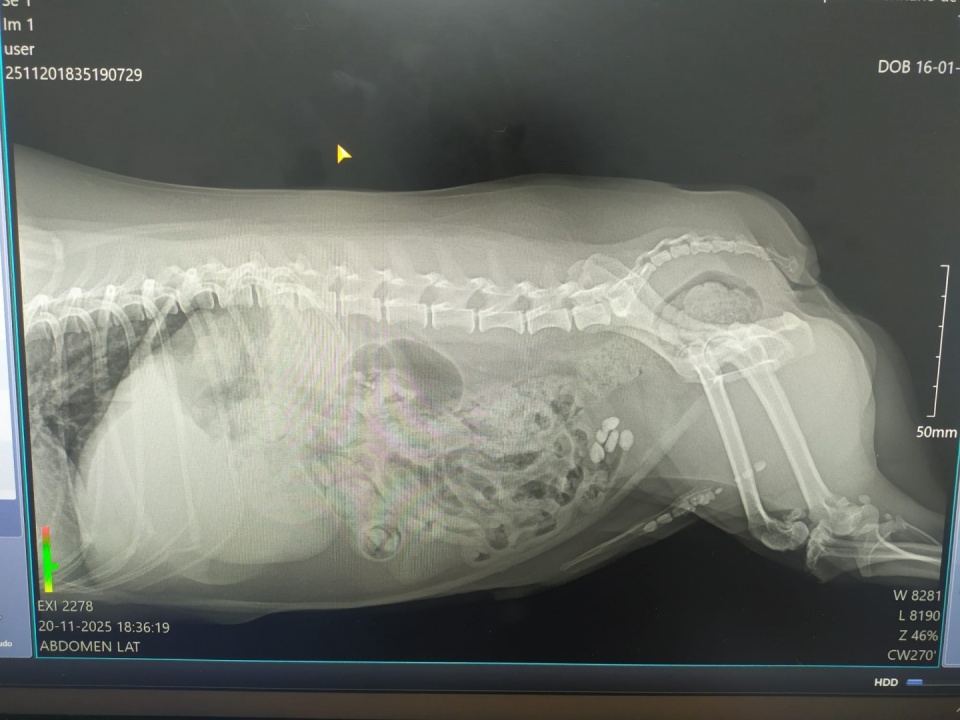

Sem qualquer aviso, este mês o pesadelo regressou: o Kiko voltou a produzir cálculos na bexiga e nos rins, criando um novo bloqueio da uretra.

No dia 20 de novembro, foi levado de urgência ao hospital veterinário com sangramento e incapacidade de urinar. Depois dos exames, devido à idade e a problemas hepáticos, foi-nos dado um cenário devastador: eutanásia ou uma cirurgia de alto risco, com possibilidade de não resistir ao procedimento.

No dia 21 de novembro, foi operado e foram-lhe removidos 23 cálculos da bexiga e da uretra.